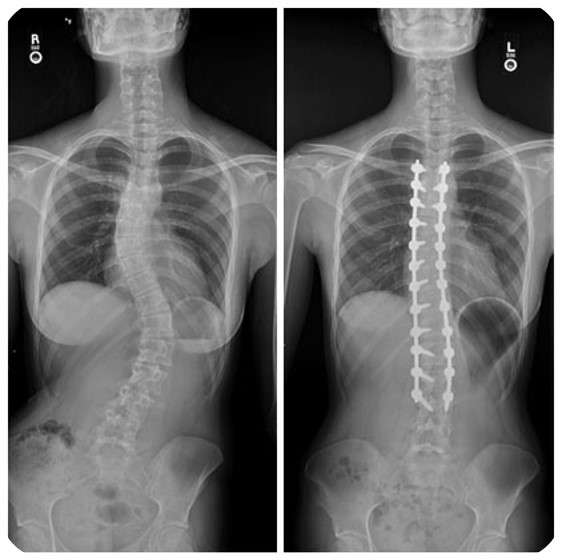

ProFlex Spine es un tratamiento mínimamente invasivo para la escoliosis idiopática del adolescente. Actúa como un “corsé interno activo”, sin las limitaciones del corsé externo ni la rigidez de la cirugía tradicional.

Está fabricado con aleaciones metálicas inteligentes (SMA) que se adaptan al crecimiento manteniendo la movilidad de la columna.

La cirugía incorpora las tecnologías más avanzadas, como navegación por TC intraoperatorio y asistencia robótica, para una colocación precisa y segura.